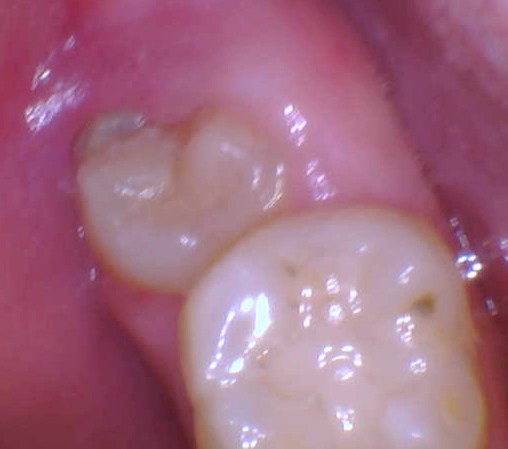

Pictures of wisdom teeth with a gum flap

Sometimes the wisdom teeth can be impacted just ever so slightly and it'll cause a tiny flap of gum at the top end of the tooth. This flap is a plaque and food trap which periodically causes the tooth to be inflamed from time to time.

Much more severe gum flap that is being chewed on by the opposing upper wisdom tooth: